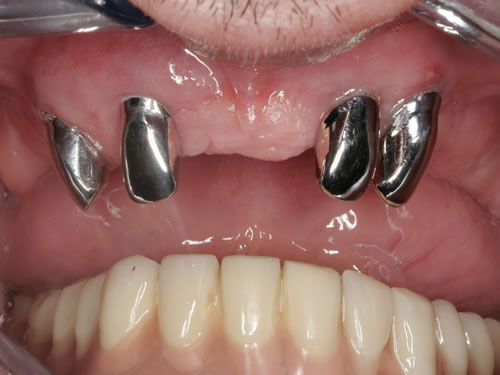

Wir begleiten in den nächsten Abschnitten eine 46-jährige Patientin (Frau W.), die bereits im Alter von 28 Jahren alle Zähne im Ober- und Unterkiefer verloren hat. Sie trägt seit 18 Jahren Prothesen. In den ersten Jahren war sie damit zufrieden. Dann wurden immer häufiger Unterfütterungen und schließlich Neuanfertigungen notwendig. Die Unterkieferprothese findet inzwischen überhaupt keinen Halt mehr, da der Kiefer sehr flach geworden ist. Im Oberkiefer wird die Gaumenplatte als sehr störend empfunden. Frau W. spricht außer Deutsch sechs Fremdsprachen und hat über viele Jahre an einer Waldorfschule Russisch unterrichtet. Das deutliche Sprechen fiel ihr aber immer schwerer, sodass sie schließlich die Lehrtätigkeit aufgegeben hat. Sie sucht jedoch verzweifelt nach einer Lösung, da ihr der Beruf fehlt.

Bei der ersten Untersuchung in der Praxis hat Frau W. zunächst den Anamnesebogen ausgefüllt. Sie ist nie ernstlich krank gewesen und nimmt nur gelegentlich eine Kopfschmerztablette. In einem ausführlichen Gespräch berichtet sie ihrem Zahnarzt über die Schwierigkeiten mit den Prothesen. Nach einer ersten Untersuchung kann ihr der Zahnarzt Mut machen. Die Kieferverhältnisse sind zwar sehr ungünstig, doch so, dass eine Einpflanzung noch möglich ist. Die vorhandenen Prothesen weisen keine Mängel auf, finden aber keinen Halt. Beide Prothesen sollen nach der Einpflanzung weiter getragen werden. Nach einem Kieferabdruck wird eine Platte für den Unterkiefer angefertigt, auf der Metallkugeln befestigt sind. Sie wird wie eine Prothese eingesetzt, und es wird eine Röntgenaufnahme gemacht, die anschließend vom Zahnarzt genau vermessen wird. Es ergibt sich, dass noch eine Resthöhe von 15 mm vorhanden ist. Da auch die Breite des Kiefers ausreicht, wird ihr die Einpflanzung von vier künstlichen Zahnwurzeln empfohlen. Für ihre spezielle Kieferform ist dies die beste Lösung.

Für den Oberkiefer ist eine CT-Untersuchung notwendig, die ebenfalls mit einer Schablone durchgeführt wird. Auswertung, Planung und Implantations-Simulationen ergeben, dass sechs Implantate im vorderen Kieferabschnitt verankert werden können. Auch die Qualität des Knochens lässt eine Einpflanzung ohne weitere Maßnahmen zu. Diese Behandlung soll nach der Versorgung des Unterkiefers erfolgen.

Unsere Patientin fragt nach dem genauen Ablauf der Behandlung und nach der Höhe der Kosten. Die einzelnen Behandlungsschritte und die notwendige Vorbereitung werden erläutert, außerdem wird ein Kostenplan erstellt. Die Pfeiler sollen drei Monate unter der Schleimhaut einwachsen und dann Teleskopkronen und ein Steg angefertigt werden, auf dem die Prothese Halt findet. An einem Kiefermodell wird Frau W. die Art der Versorgung erklärt und das Einrasten der Prothese auf dem Steg gezeigt. Sie ist mit der vorgeschlagenen Behandlung einverstanden.

Für den zahnlosen Ober- und Unterkiefer werden dies häufiger Stegkonstruktionen oder Teleskopversorgungen sein (Abb. 8.8 bis 8.16).